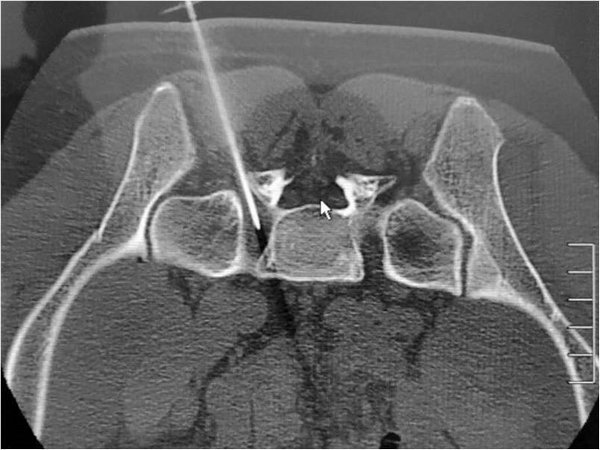

CT引导下选择性腰、骶神经根阻滞术是在CT机引导下,对可能引起神经根痛的病变神经进行穿刺阻滞的微创技术,由于CT扫描软组织分辨率高,可清晰显示神经根、背根神经节和周围组织结构,在CT引导下能准确选择最佳穿刺点、穿刺角度及深度,使针尖准确到达神经根周围位置,并能避开血管等重要结构,使手术安全、准确,用药量少,并大大降低了并发症的发生率。

穿刺针精准刺入骶1孔